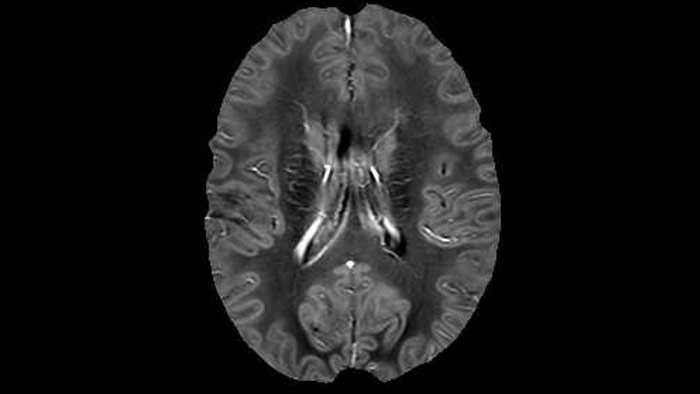

Dr. Rauscher says, “With better gradients we can use a shorter echo spacing on the spin echo, so we get better sampling of the rapidly decaying myelin signal, which typically has T2 of around 10-20 milliseconds at 3 Tesla. If we can reduce echo spacing from about 8 to 5-6 milliseconds, we get a much better sampling of the short decay component and increase our SNR, which is a big advantage. The same is true for multi-echo gradient echo which we use for susceptibility mapping and for mapping venous vessels in MS.”

QSM based on a Compressed SENSE multi-echo SWI.